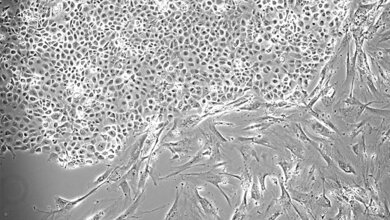

Viren sind winzig - nur unter dem Elektronenmikroskop werden die kleinen Partikel sichtbar. In „freier Wildbahn“ überleben sie in den meisten Fällen nicht sehr lange. Um ihr Fortbestehen zu sichern, benötigen Viren immer eine sogenannte Wirtszelle. Dort nisten sie sich ein und vermehren sich – bis sie die Zelle dadurch zerstört haben. Die freigewordenen Viren infizieren dann neue Zellen. Diese Eigenschaft versuchen die Wissenschaftler für die Krebsmedizin nutzbar zu machen.

„Mit Hilfe gentechnischer Methoden verändern wir Grippeviren so, dass sie in der Lage sind, Tumorzellen bei Patienten mit einem nicht-kleinzelligen Lungenkarzinom (NKLK) anzugreifen und zu zerstören“, erklärt Professor Dr. Stephan Ludwig vom Institut für Molekulare Virologie des Universitätsklinikums Münster den Kern seiner Forschung. „NKLK-Patienten haben bisher nur sehr geringe Heilungschancen, denn diese Krebsart metastasiert sehr häufig und die gängigen Therapieoptionen wie Chemotherapie und Bestrahlung sind oft wirkungslos.“

Auch das körpereigene Abwehrsystem hat dem Tumor kaum etwas entgegenzusetzen. Denn dieser hat eine perfide Überlebensstrategie entwickelt: die herbeieilenden Abwehrzellen werden einer Art „Gehirnwäsche“ unterzogen, so dass sie den Tumor nicht mehr angreifen können. Vielmehr zwingt er sie dazu, ihn beim Wachstum und bei der Ausbreitung im Körper zu unterstützen. Sind die Tumorzellen allerdings mit Grippeviren infiziert, löst das eine starke Immunantwort gegen die befallenen Zellen aus.